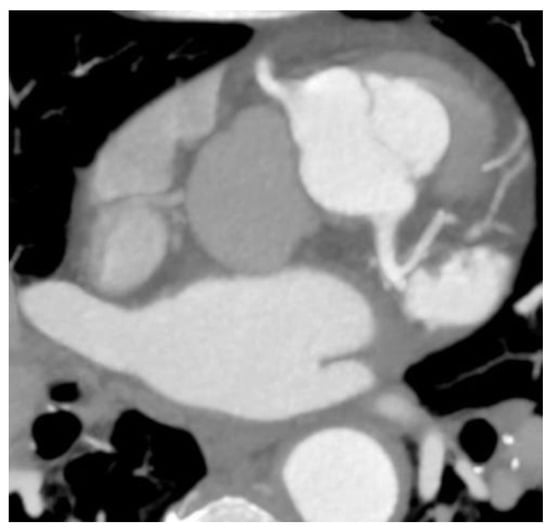

Two cases of anomalous origin of the left main coronary artery arising from the right sinus were found, as depicted in Figure 1.

Figure 1. Anomaly of the origin of the left main coronary artery arising from the right anterior sinus. (a) CCTA volume rendered 3D images show the vascular tree anatomy, in which an origin anomaly is present. The left main coronary artery arises from the right sinus immediately above the right coronary artery with an anomalous course anteriorly to the left pulmonary artery towards the anterior interventricular sulcus, where it forms the anterior interventricular and circumflex arteries. The right coronary artery is well developed, with increased dimensions and the presence of a well-developed marginal branch and collateral circulation. Diffuse atheromatous infiltration of the left coronary tree is also present; (b) CTAA volume rendered 3D images show the vascular tree anatomy in relation to the left ventricle.